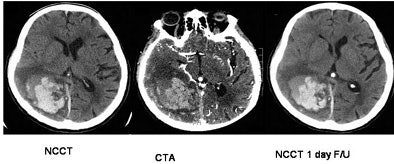

| Top, a patient with CTA spot sign (+VE) and hematoma expansion; bottom, a patient with CTA spot sign (-VE) and no expansion. Patients presenting with the spot sign at CT were more than eight times as likely to have hematoma expansion. Images courtesy of Dr. Richard Aviv. |